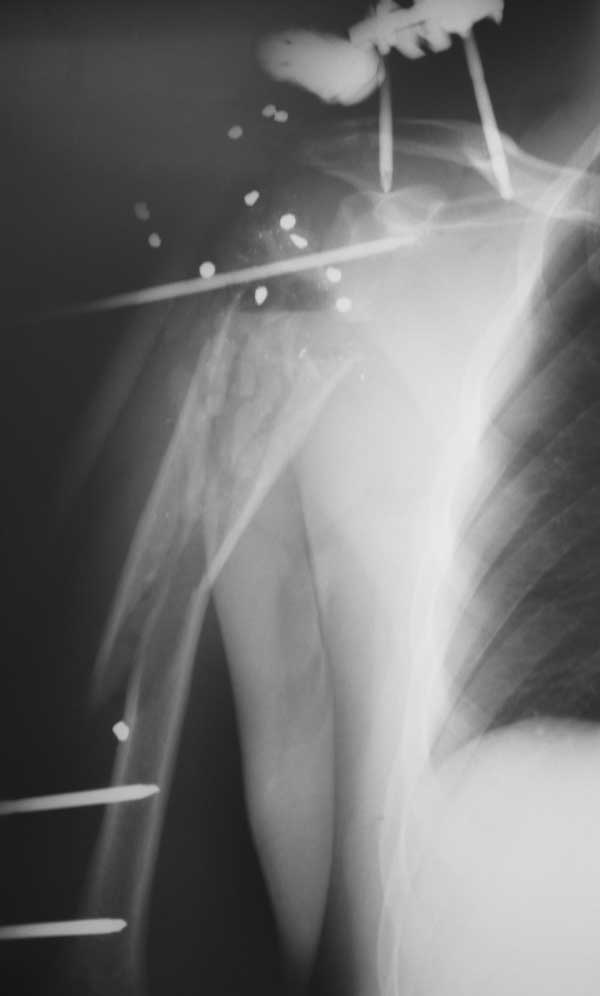

Молодой человек 25 лет поступил с огнестрельным ранением области плечевого сустава.

травма 12.05.12 - огестрельное ранение правого плечевого сустава, открытый многооскольчатый перелом проксимального отдела плеча с переходом на диафиз. стреляли практически вупор. Входное отверстие округлое диам 3 см по передней поверхности дельтовидной области, выходных отверстий множество диам до 0,5 см больше по задне верхней поверхности дельтовидной области. при поступлении - ПХО при ревизии - удален пластиковый пыж, повреждена вся дельтовидная мышца частично повреждены надостная подостная мышцы, капсула сустава разорвана в клочья,сухожилия ротаторной манжеты также разорваны в кашу, головка плеча - ее не было - просто костная каша в ране, кроме того выявлен перелом акромиона. гленоид практически не пострадал. Рана промыта нежизнеспособные ткани иссечены, костная крошка удалена. швы на рану, перелом стабилизирорван стержневым аппаратом. На сегодняшний день - рана без воспаления, заживление первичное. Движения в кисти, локтевом суставе в полном объеме. Вопрос к уважаемому сообществу - что делать? С уважением Леонид Пак